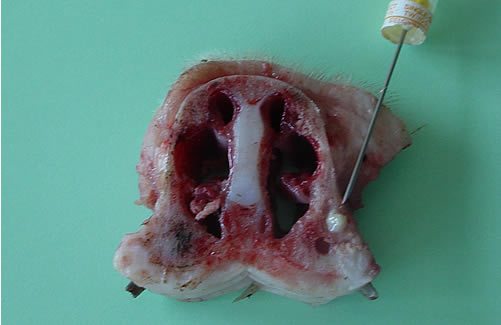

Les têtes sont sciées horizontalement pour séparer les maxillaires afin de réaliser des radiographies sans superposition d’images.

Sur le porc n°1: l’abcès sous-cutané ne présente pas de fistule. Une coupe transversale du groin au niveau de l’incisive I3 permet de visualiser l’abcès dentaire.

Les bactéries isolées de l’abcès dentaire sont des contaminants ordinaires de l’environnement : Enterobacter agglomerans , Corynebacterium sp , Pseudomonas sp.»

« Hypothèse d’une contamination ascendante (probablement à l’occasion de la coupe des coin et canine) conduisant à la formation d’abcès (dentaire et sous-cutané) par diffusion locale des bactéries. La présence de l’abcès de la face qui s’est développé indépendamment d’un lien visible avec les dents peut aussi résulter de morsures consécutives à des batailles.» |